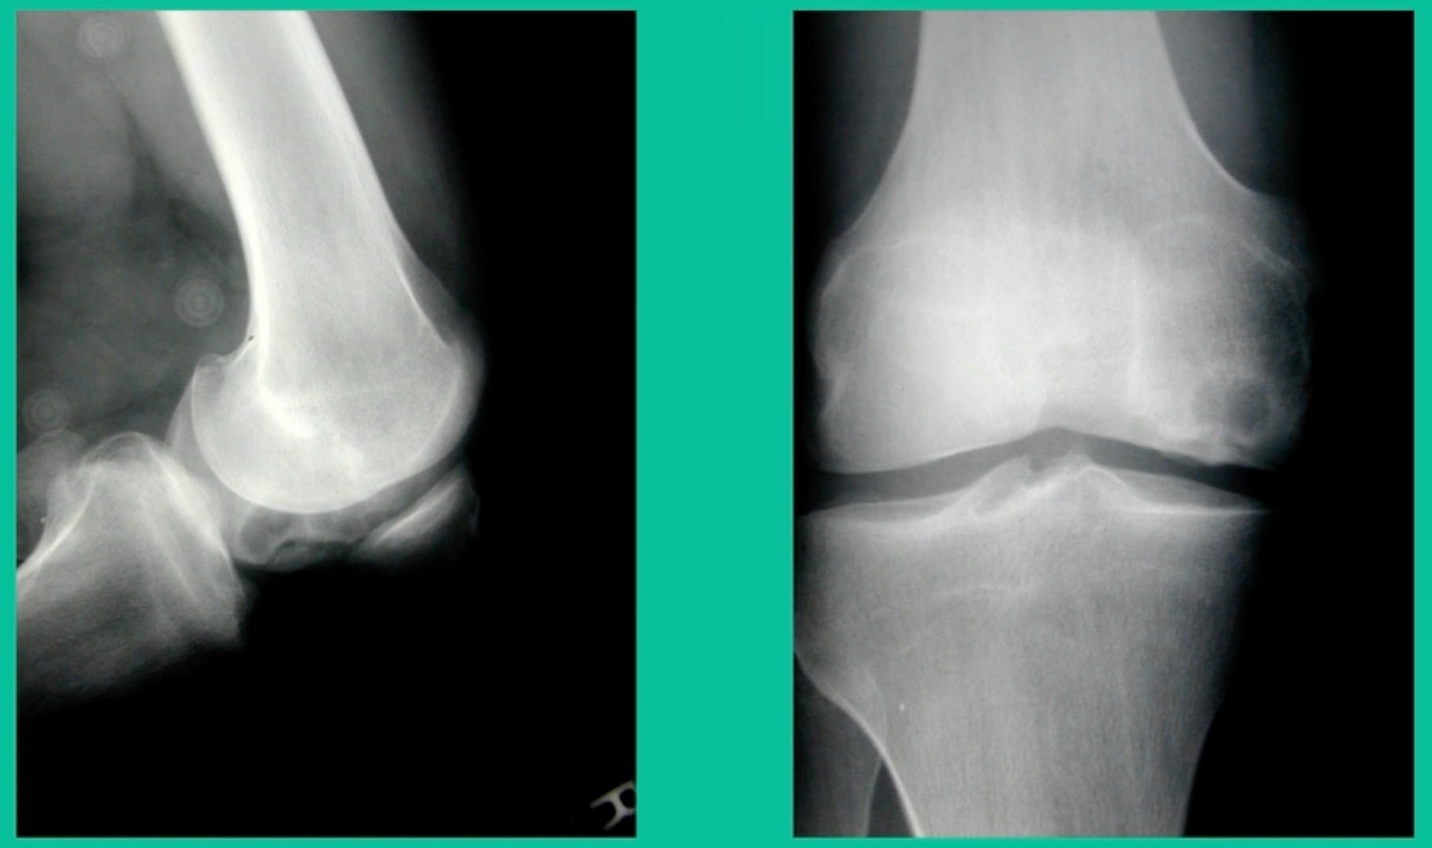

Now a couple of quick cases. This is juvenile OCD. This is the first series of three or four, just juveniles. 14-year-old, intermittent knee pain, lateral femoral condyle OCD (Figure 1).

I thought I might be able to fix it. I had the conversation with the family, get in there, started taking it apart with a Vanguard elevator grasper. Behold, it’s really just cartilage fragments (Figure 2).

There’s two or three of them. We debrided it. It felt normal in six weeks, no complaints in three years. What are the results of juvenile debridement? They’re actually profoundly good. You would never expect this in the scheme of things, but the natural history of removing the piece is actually very good in the juvenile patient. However, once again, fix it if you can. Debride it, if you can’t. If they get symptoms, we restore it, and then never leave unstable fragments.